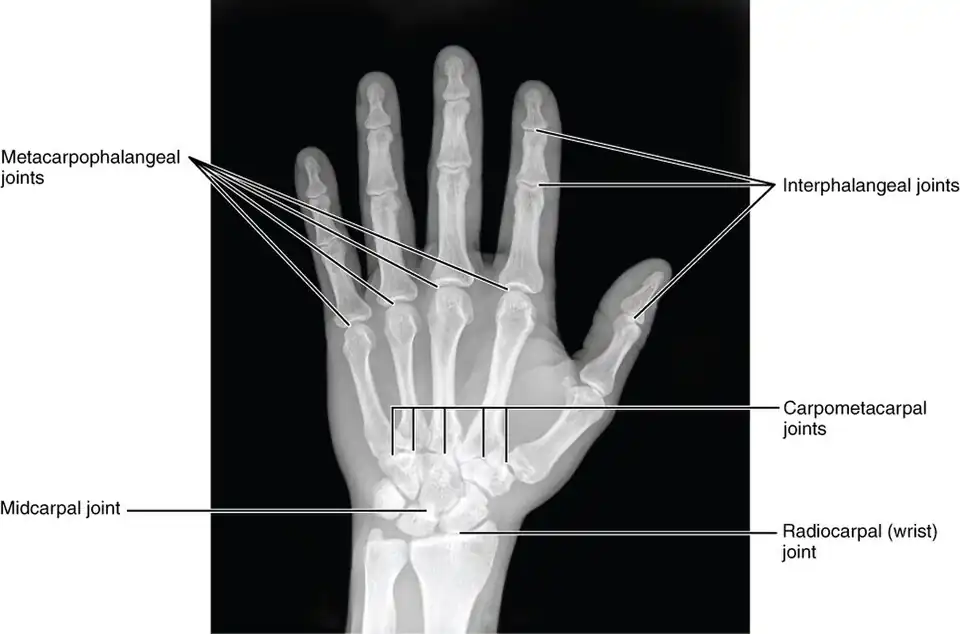

The intercarpal joints (joints of the carpal bones of the wrist) can be subdivided into three sets of joints (also called articulations): Those of the proximal row of carpal bones, those of the distal row of carpal bones, and those of the two rows with each other.

The bones in each carpal row interlock with each other and each row can therefore be considered a single joint. In the proximal row a limited degree of mobility is possible, but the bones of the distal row are connected to each other and to the metacarpal bones by strong ligaments that make this row and the metacarpus a functional entity. [1]

Midcarpal

- See Midcarpal joint

These four surfaces form two joints: (1) a proximal, the wrist-joint proper; and (2) a distal, the mid-carpal joint.

Mid-carpal joint

- See Midcarpal joint